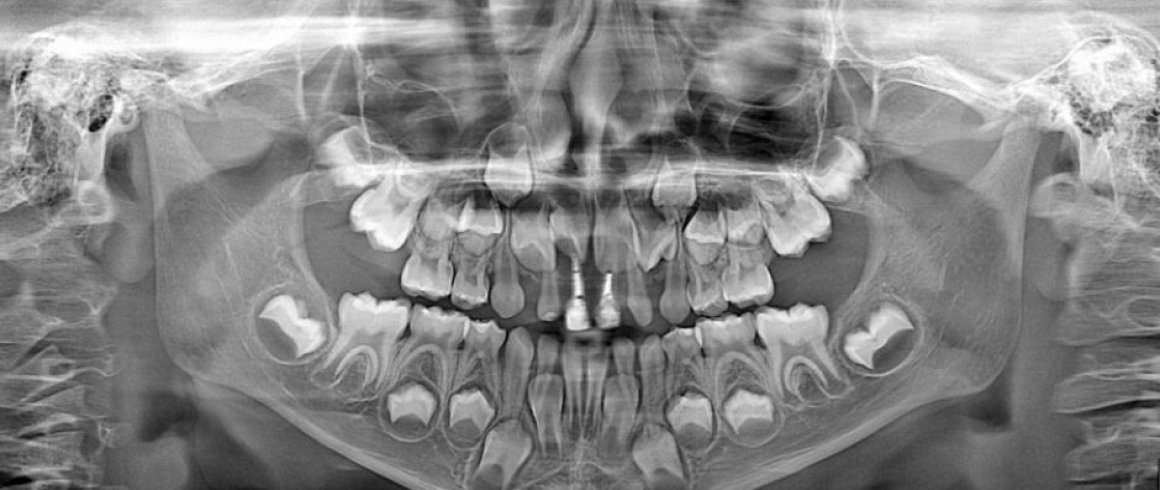

- Panorámica

- Radiografías Extraorales